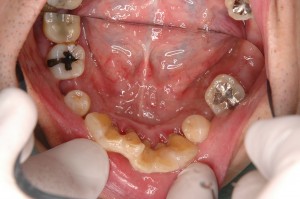

上顎は13-23ブリッジおよびRPD、下顎はインプラント支台のボーンアンカードブリッジとする計画を立案、治療を行いました。

全顎的な歯周治療の後、インプラント治療へと移行しました。

インプラント埋入に際し、サージカルガイドを保持する目的で、抜歯予定の46を残存させ、他部位埋入後抜歯後即時埋入を行いました。